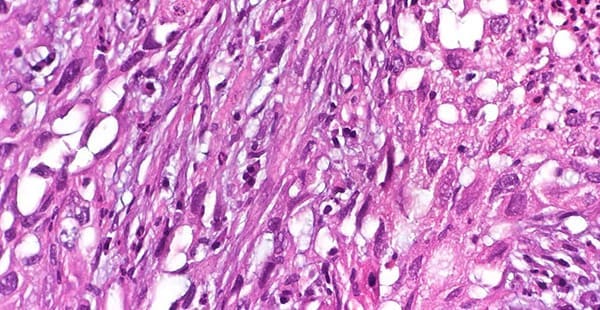

There are several defining characteristics that can help identify sarcomatoid cells:

- An oval, elongated shape with a large nucleus

- Multiple nuclei in some cells

- Unstructured formation in fibrous nodes or lesions

- Distant cell formation that is faster to metastasize than other cell types

Sarcomatoid cells are notable for their oblong, spindle shape. As such, sarcomatoid mesothelioma is also referred to as spindle cell or sarcomatous mesothelioma.

A biopsy is the most important step in making an accurate sarcomatoid mesothelioma diagnosis. Cell type can be determined through a tissue biopsy and analyses of the sample, such as immunohistochemistry. This is a staining method that uses antibodies to identify mesothelioma-specific proteins in the tissue sample.

Through an immunohistochemical stain, a pathologist can identify if a tumor is benign or malignant.

Several immunohistochemical markers can indicate mesothelioma. Sarcomatoid mesotheliomas stain positively for pancytokeratin, WT1 and/or podoplanin, a marker also known as D2-40. A minority of sarcomatoid mesotheliomas also stain positively for calretinin.